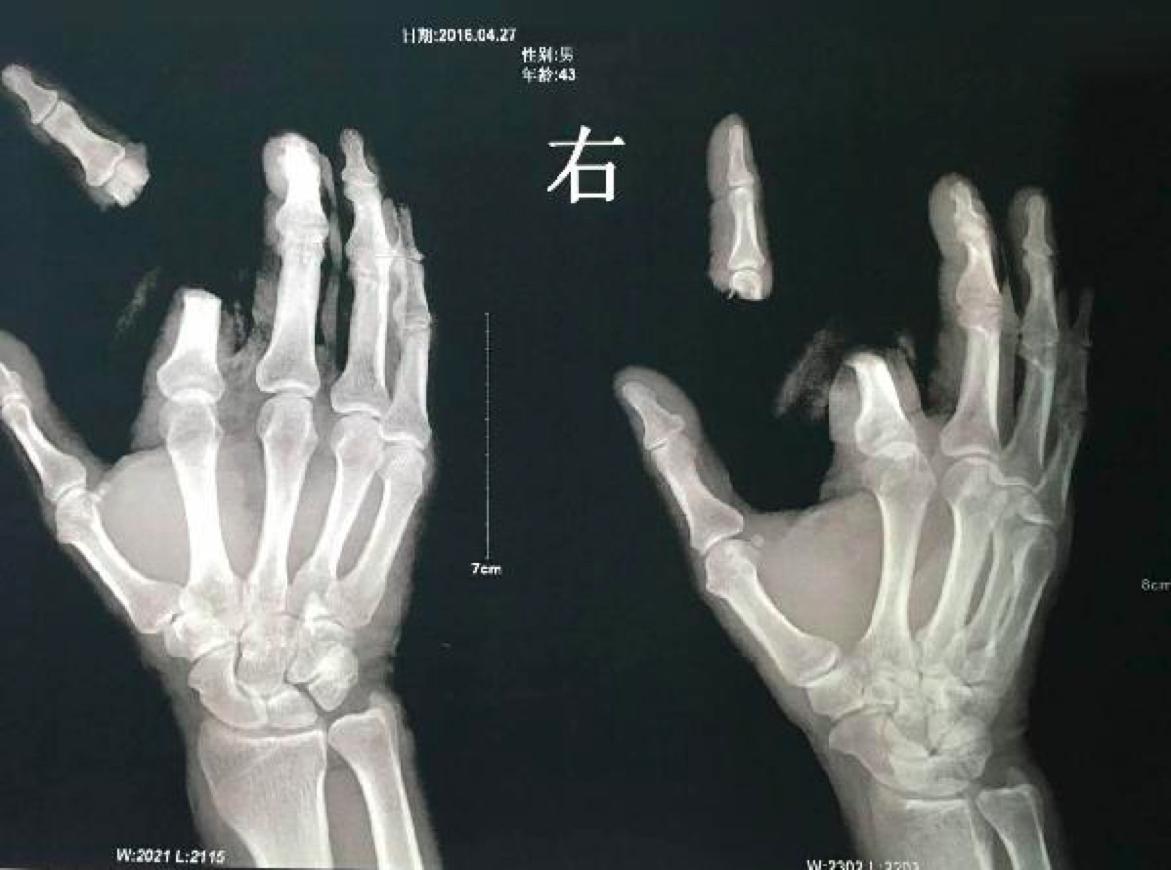

在湖南常德,曾有一名男子不小心将一只隐翅虫捏死,因皮肤沾上了少许毒液,随后开始出现水泡。因听信隐翅虫的毒液可致人死亡的谣传,该男子在情急之下竟拿起菜刀,将自己的右手食指砍下。家人将其送医后,手指才侥幸接回。

断指男子X光照片